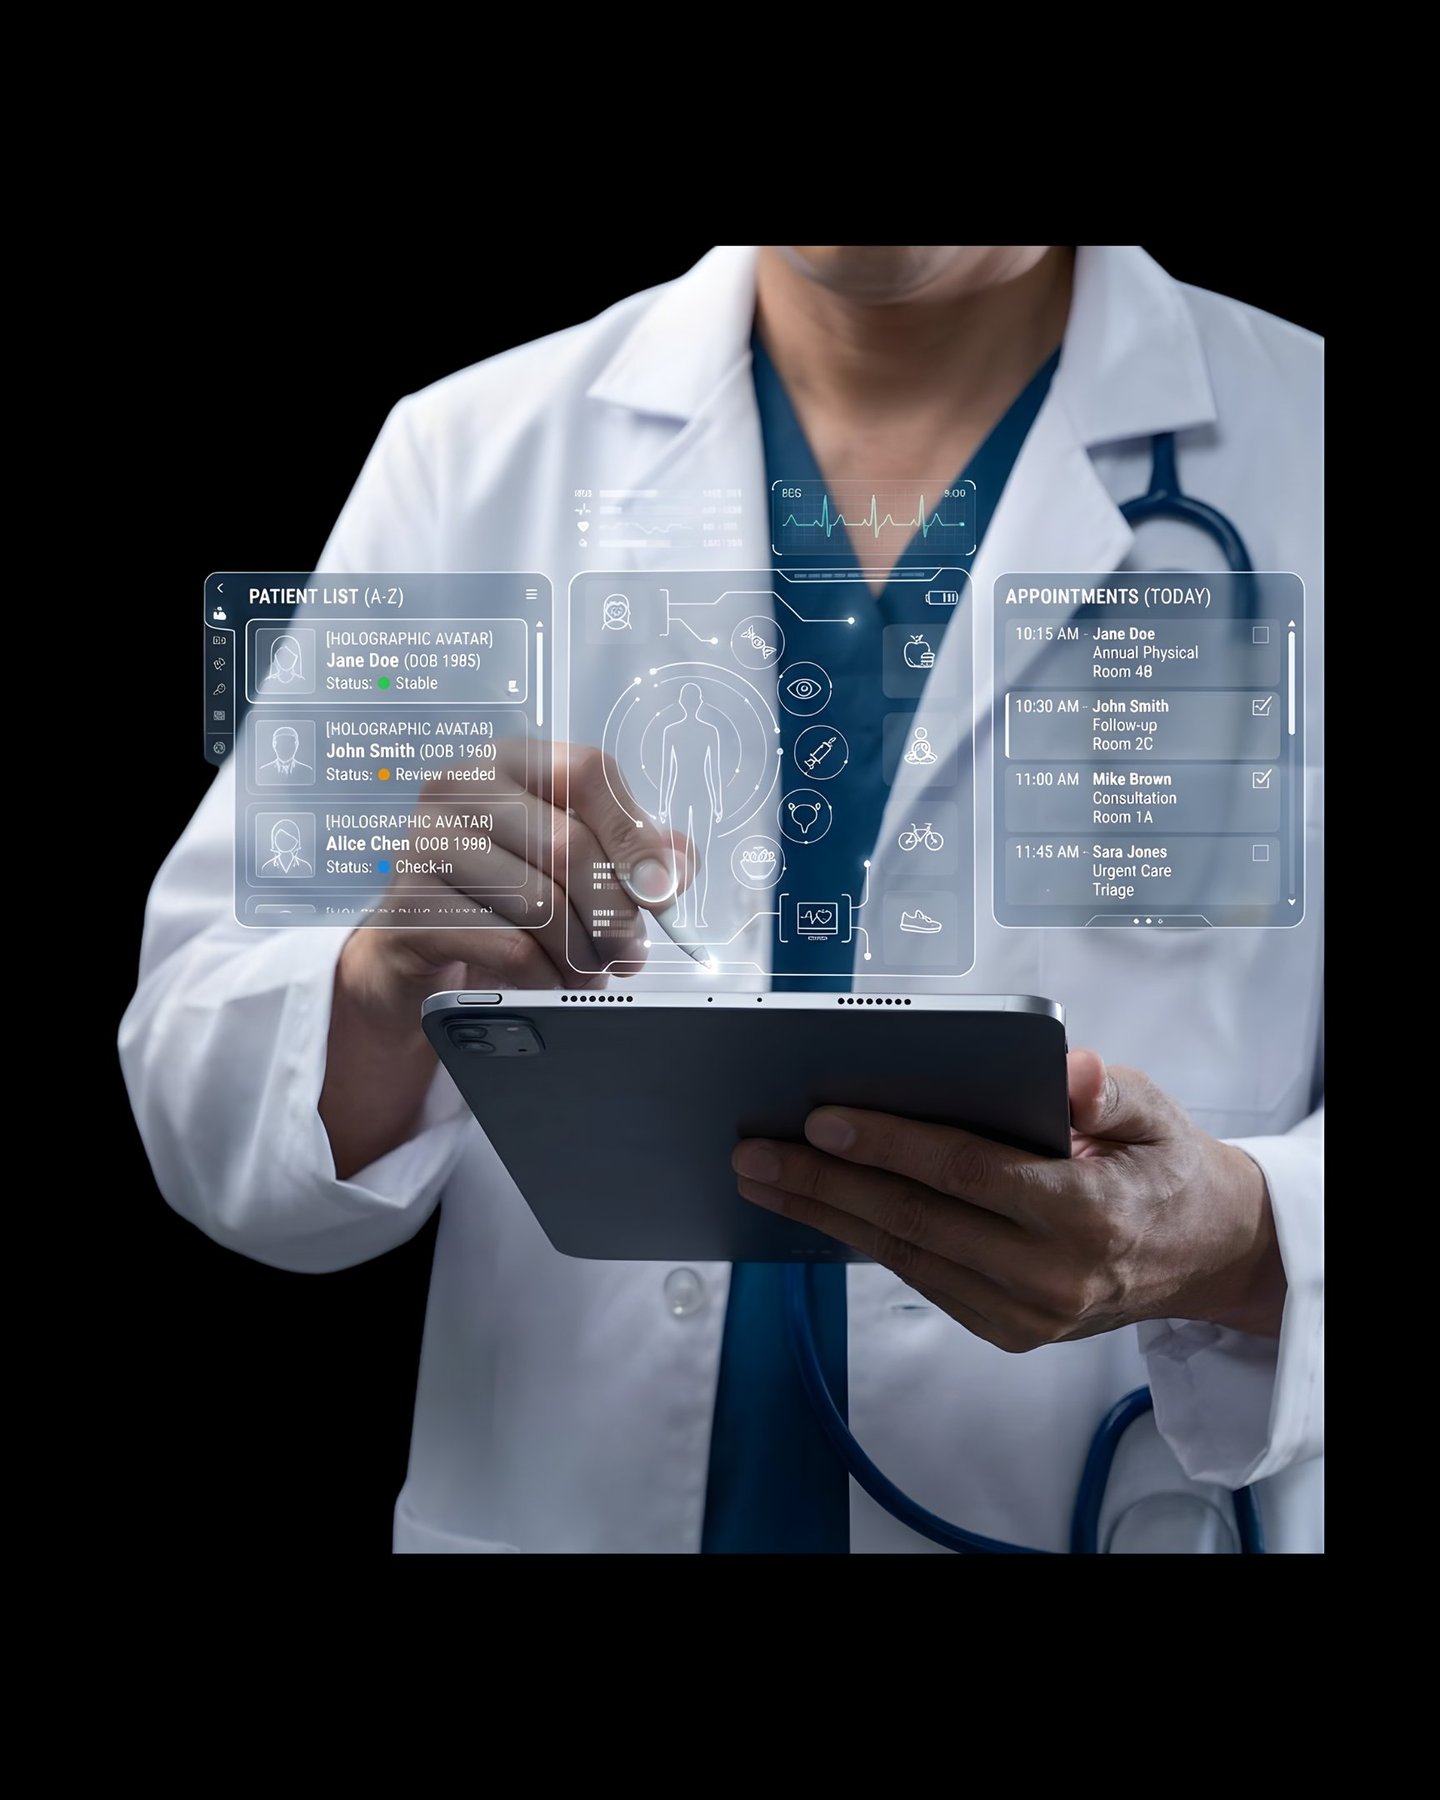

PHIA.CARE helps doctors run smarter Clinics / Polyclinics with AI-assisted prescriptions, instant risk reports, and fully digital patient management—so you focus on treatment, not paperwork.

A future-ready healthcare platform built for the speed, scale, and intelligence required by today’s Hospitals and Clinics.

Your Smart Digital Front-Desk

Track all appointments and enquiries in one place in your admin profile.

We empower Doctors, clinics and hospitals with our technology-enabled platform, enabling efficient and structured patient management through single account and health risk evaluations at the OPD level.

Intelligent Health Insights

With built-in risk assessment, smart analytics, and concise patient summaries, doctors can make faster, more accurate decisions while shifting towards preventive care.

Phia.Care brings all patient data—visits, prescriptions, reports, and history—into one seamless platform, reducing manual work and saving time.